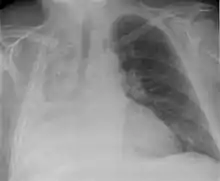

Atelectasis of a person's right lung | |

Clinically significant atelectasis is generally visible on chest X-ray; findings can include lung opacification and/or loss of lung volume. Post-surgical atelectasis will be bibasal in pattern. Chest CT or bronchoscopy may be necessary if the cause of atelectasis is not clinically apparent. Direct signs of atelectasis include displacement of interlobar fissures and mobile structures within the thorax, overinflation of the unaffected ipsilateral lobe or contralateral lung, and opacification of the collapsed lobe. In addition to clinically significant findings on chest X-rays, patients may present with indirect signs and symptoms such as elevation of the diaphragm, shifting of the trachea, heart and mediastinum; displacement of the hilus and shifting granulomas.[10]